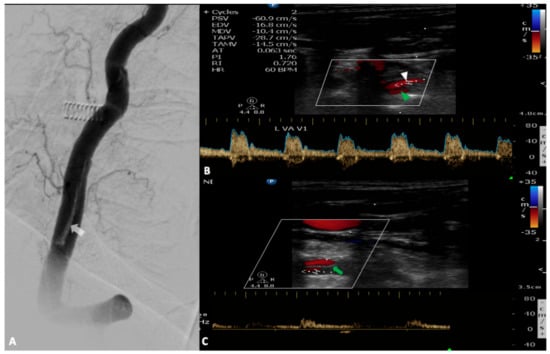

3. Vertebral Artery

5. Subclavian Steal Syndrome